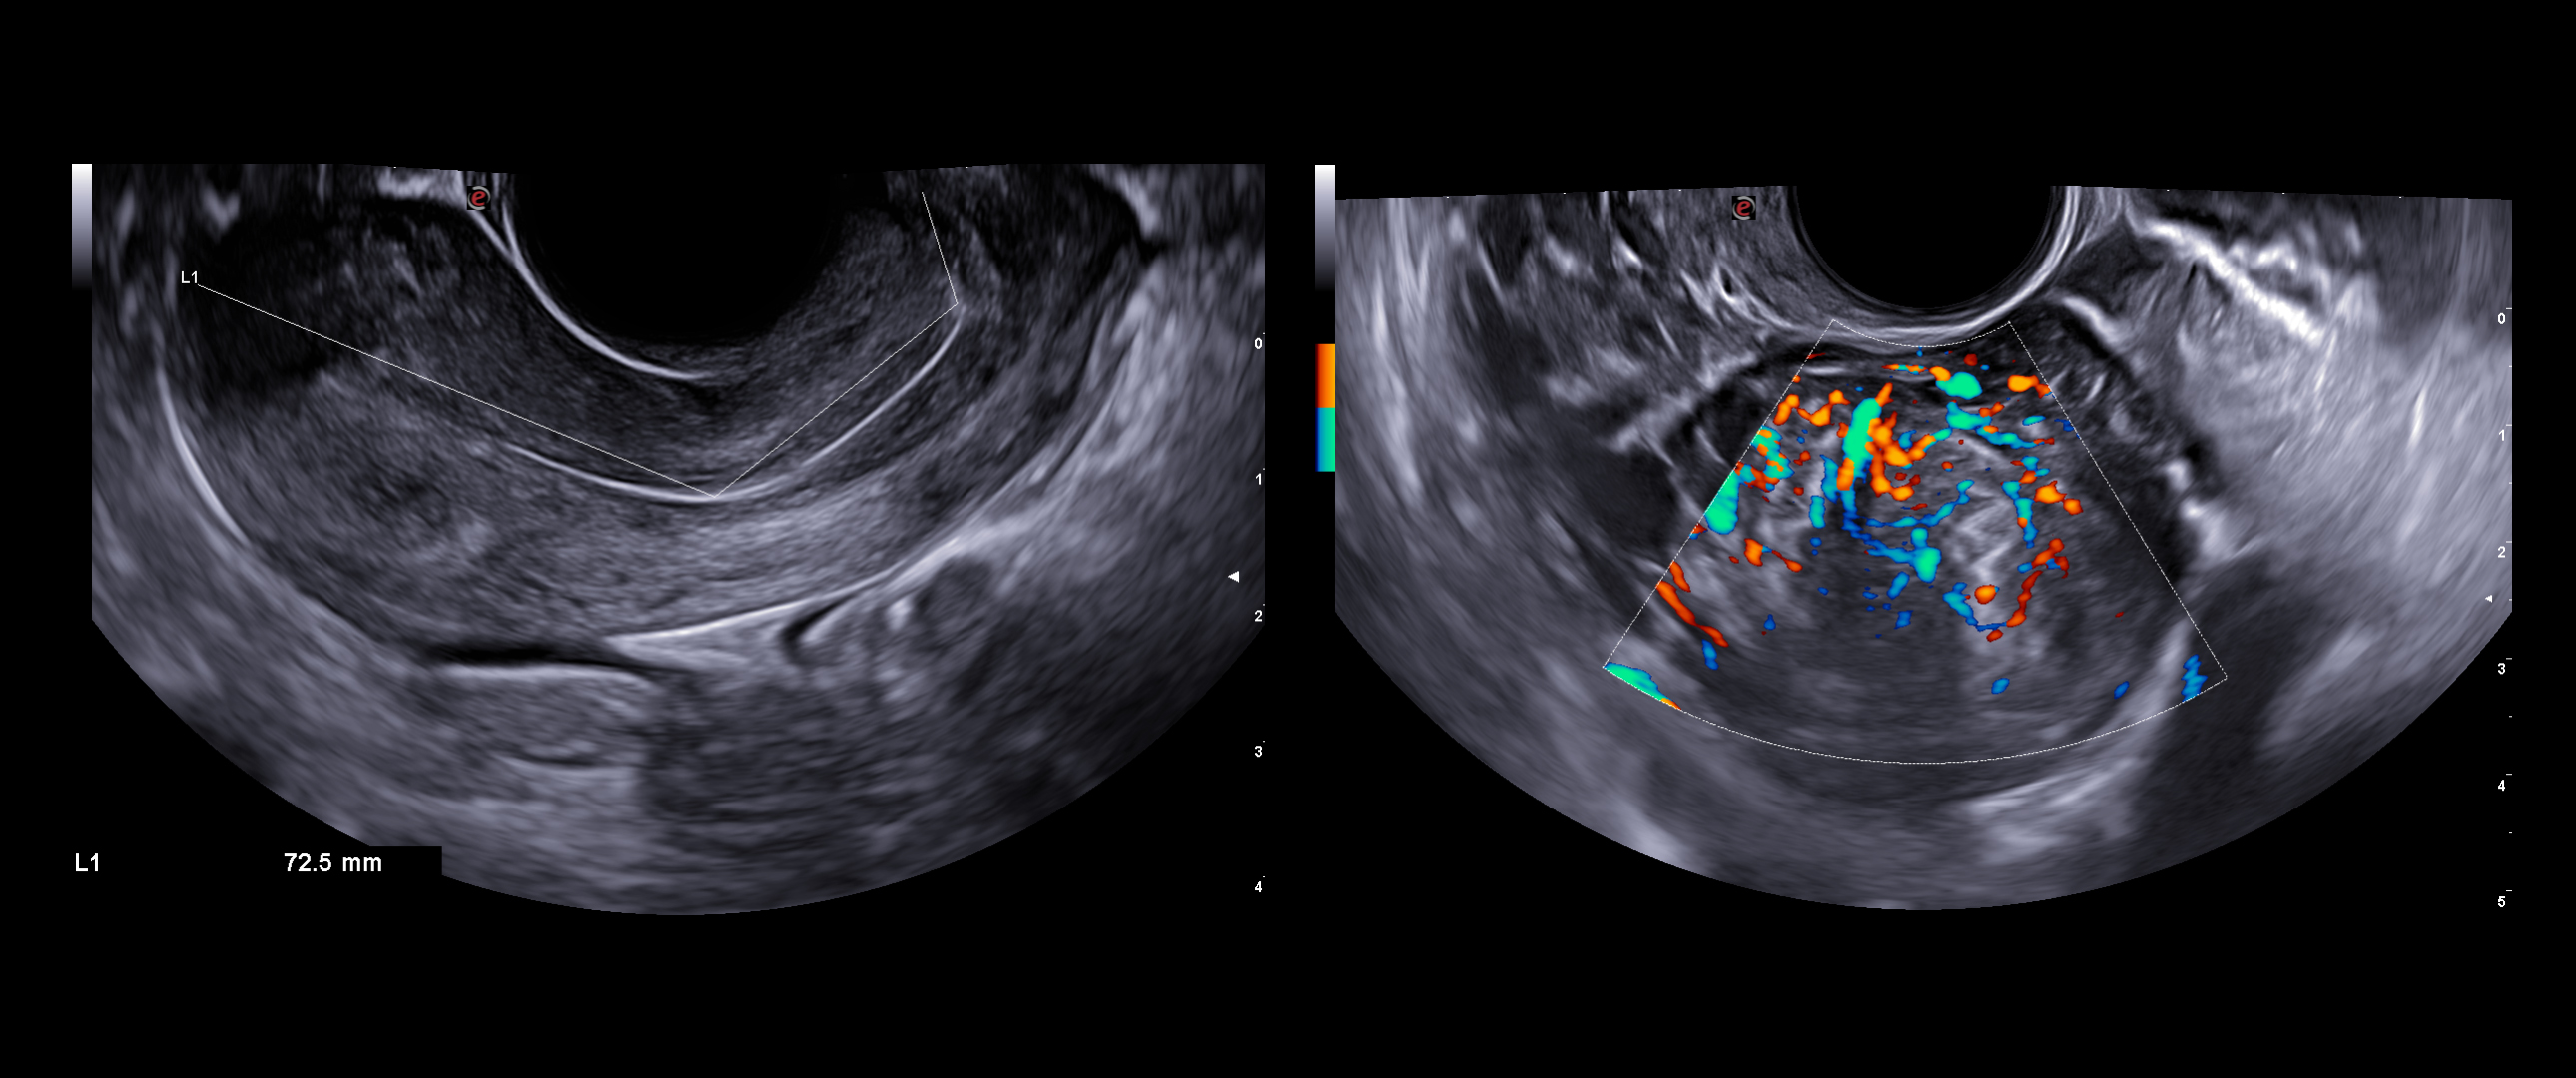

The improved vascular image quality together with the extreme sensitivity of Esaote Doppler technologies (Power Doppler and microV) allow the detection of tiny vessels, to precisely assess the extent of the vascularization, to provide you with a better understanding of certain pelvic abnormalities such as fibroids, polyps, or endometriosis conditions.

Virtual Navigator is the revolutionary Esaote technology for fusion imaging. Suitable applications for this methodology include deep infiltrating endometriosis (DIE), where the combination of magnetic resonance imaging (MRI) and transvaginal ultrasound (TVUS) considerably optimizes the detection of this pathology.